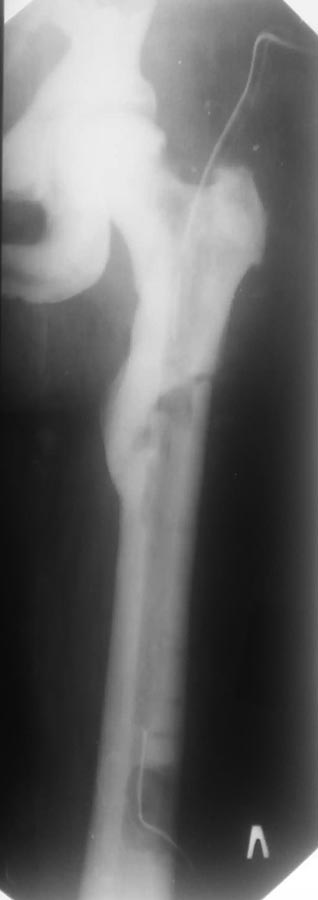

Уважаемые коллеги. Огромное спасибо за ваши рекомендации, которые очень

понадобились нам во время операции. Больную прооперировали 01.04.15г.

Изогнутый конец штифта резецировали, затем просверлили отверстие в

штифте, сделали узел из спицы Илизарова и попытались удалить скользящим

молотком–  без эффекта. Для уменьшения демпферирования в дистальном

конце бедра наложили кольцо от аппарата с 3-мя спицами (спицы проведены

без особого труда) для противоупора, но даже при этом штифт не

шелохнулся! В связи с чем открылись дистально - костно-мозгового канала

нет, но кость поддаётся сверлению (наверное сказывается остеопороз от

иммобилизации и гиподинамии). Дистальный конец штифта освободили от

костной ткани, добили на 1 см. и удалили антеградно. Далее приточно–

отточное дренирование, антибиотикотерапия с учётом антибиотикограммы.

Алишер Дадабаев

ГКБ№  1 г. Худжанд.